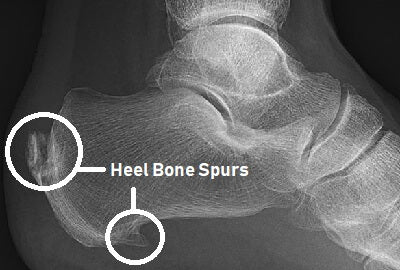

Did you have heel pain? Heel spur may be the reason . Read more to know more about heel spur. A calcaneal spur, also known as a heel spur, is a bony growth that occurs on the bottom of the heel bone. This condition is often associated with plantar fasciitis, a painful inflammation of the plantar fascia, which is a thick band of tissue that runs across the bottom of the foot. Calcaneal spurs can cause pain and discomfort, particularly when standing or walking, and can be challenging to treat.